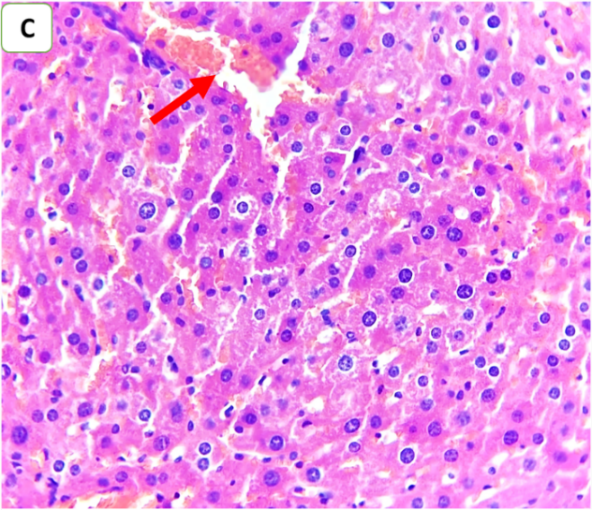

Histopathological examination was performed to evaluate the degree of hepatic injury 24 h after CLP. Compared with those in the sham group, the liver tissues in the CLP and CLP+DMSO groups were significantly damaged. Conversely, histopathological analysis of the liver in the CLP+ertugliflozin group revealed a slight degree of necroinflammation and steatosis (fig. 5, fig. 6). Fibrosis was not detected in any of the study groups.

Fig. 6: Effects of ertugliflozin on histopathological findings (6 animals in each group): A. CLP group: animals underwent CLP-induced sepsis, with a necroinflammatory grade of 3, liver tissue with vascular congestion (red arrow), hepatocytes ballooning (blue arrows), apoptotic cells (green arrow) and steatosis (yellow arrows). B. Sham group: animals in this group were anaesthetized only and then laparotomized without the induction of sepsis by CLP, and the necroinflammatory grade was zero liver tissue with vascular congestion (red arrows). C. CLP+ertugliflozin group: animals were intraperitoneally injected with ertugliflozin (20 mg/kg) 1 h before CLP, the necroinflammatory grade was zero, and vascular congestion occurred (red arrow). D. CLP+DMSO group: animals were intraperitoneally injected with DMSO (vehicle for ertugliflozin) 1 h before CLP, the necroinflammatory grade was 2, and the liver tissue exhibited mild inflammation (black arrow). Vascular congestion (red arrows). A and BandCandD X 400, HandE staining